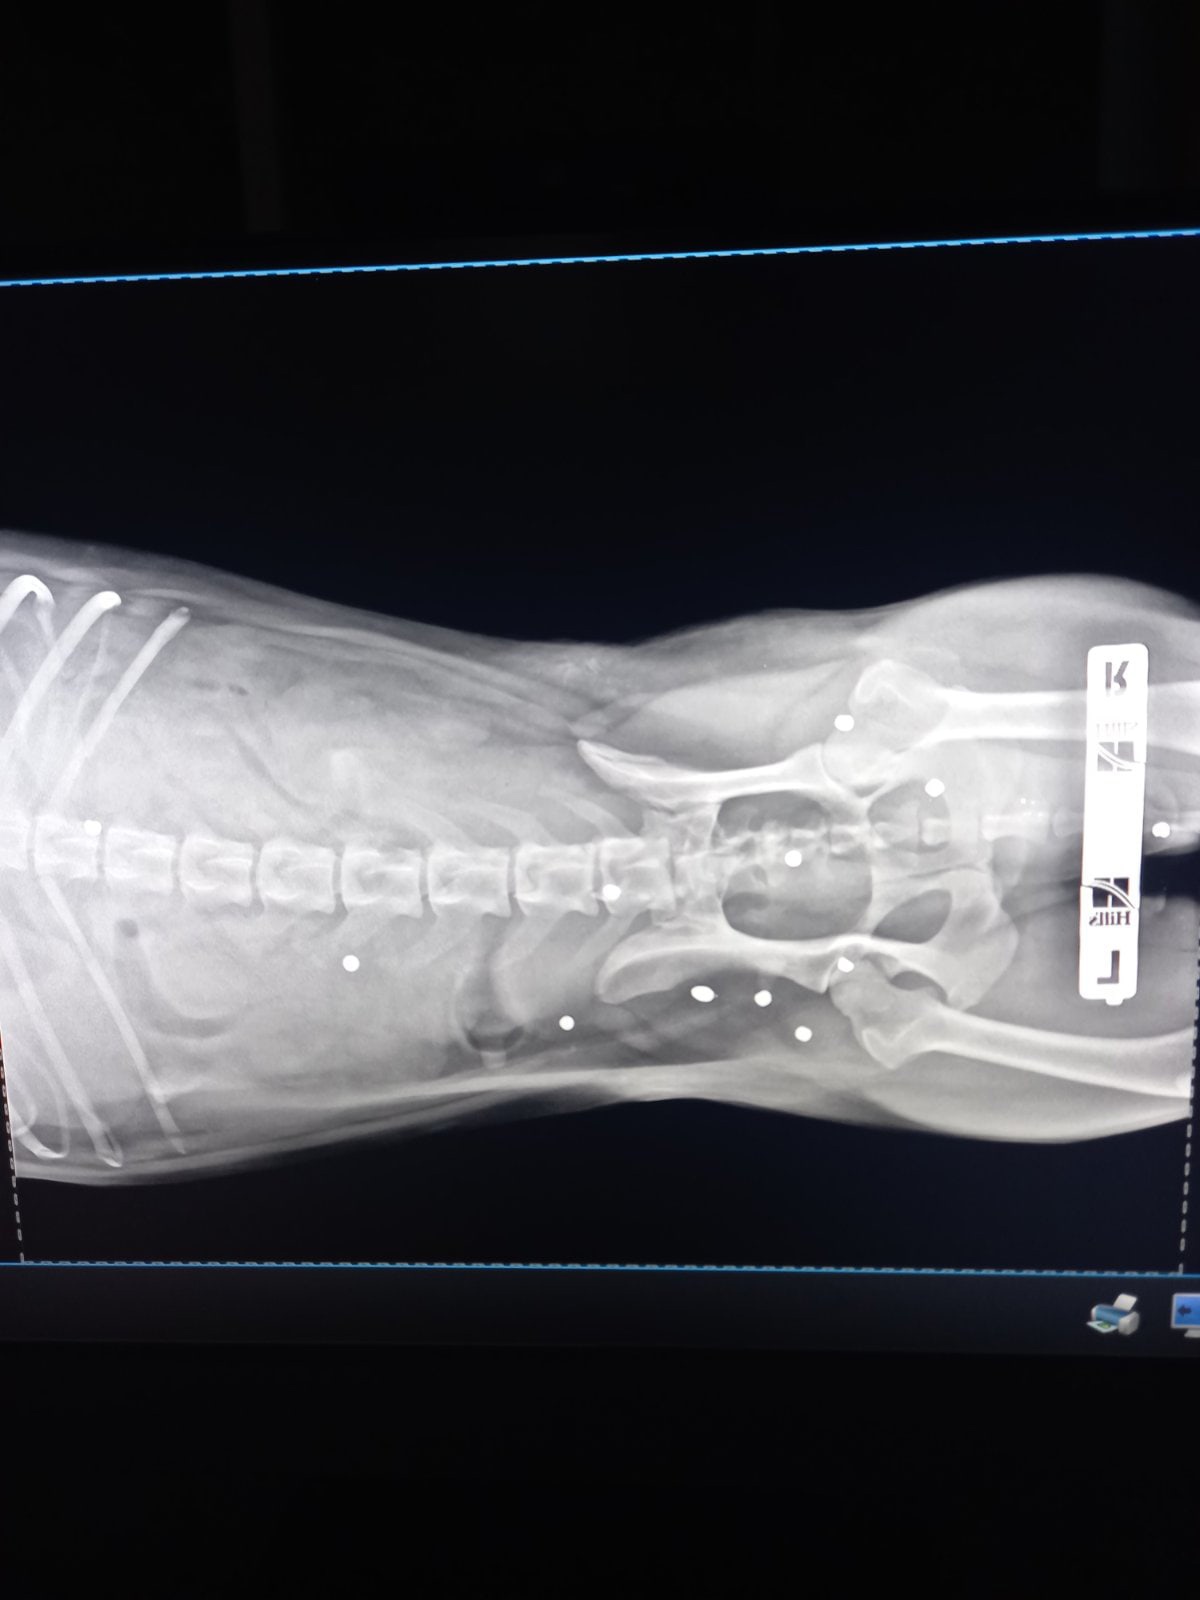

Оренбурженка связалась с волонтёрами приюта "Я - Живой". Удалось найти автомобиль, свозить животное в ветклинику. Как оказалось, её расстреляли из охотничьего ружья. В теле обнаружили 19 дробин. Не было практически ни одного живого места: повреждены голова, лапы, позвоночник, грудь, горло, живот, глаз. Врач отметил, что если бы стреляли с более близкого расстояния, то шансов выжить у бедной собаки не было бы...

Когда состояние Белоснежки стабилизировалось, воспаление сняли антибиотиками, она успокоилась и немного отошла от всего ужаса, произошедшего с ней, мы отправились на прием в клинику. После осмотра была проведена ювелирная операция по удалению дробин из головы! Быстро, качественно, нетравматично. Другие дробины удалять не стали, так как они не повредили внутренние органы, риск от операций больше, чем польза для жизни и здоровья собаки. С дробиной, застрявшей в глазу, ситуация неоднозначная. Удалять глаз очень жалко, оставили все как есть, нужно будет следить за состоянием глаза и вовремя снимать воспаление каплями.